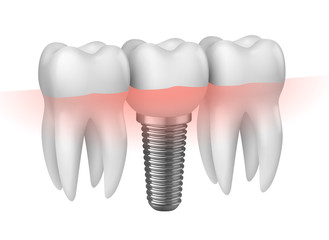

インプラント治療のメリットは、周りの歯に負担をかけず、審美性と機能性に優れた歯を手に入れられることです。インプラント治療を受けるべきかどうかお悩みの方、お口の状態を確認したい方は当院までお気軽にご相談ください。

インプラント治療の成功とは、手術の成功ではありません。インプラント治療を行ったことで、良好な口腔内を維持できてこそインプラント治療が成功したと言えます。そのためには、的確な治療計画を立案し、その通りに治療を行うためのスキルを身につけることが大切です。また、長期間にわたる治療となるため、歯科医師との信頼関係の構築も欠かせません。

インプラントは品質を10年維持できることが重要だと考えております。インプラント治療は天然歯と全く同じ機能、審美性が手に入る治療法ではありません。適切な予防ケアを続けることで、より天然歯に近い状態を長く維持できます。